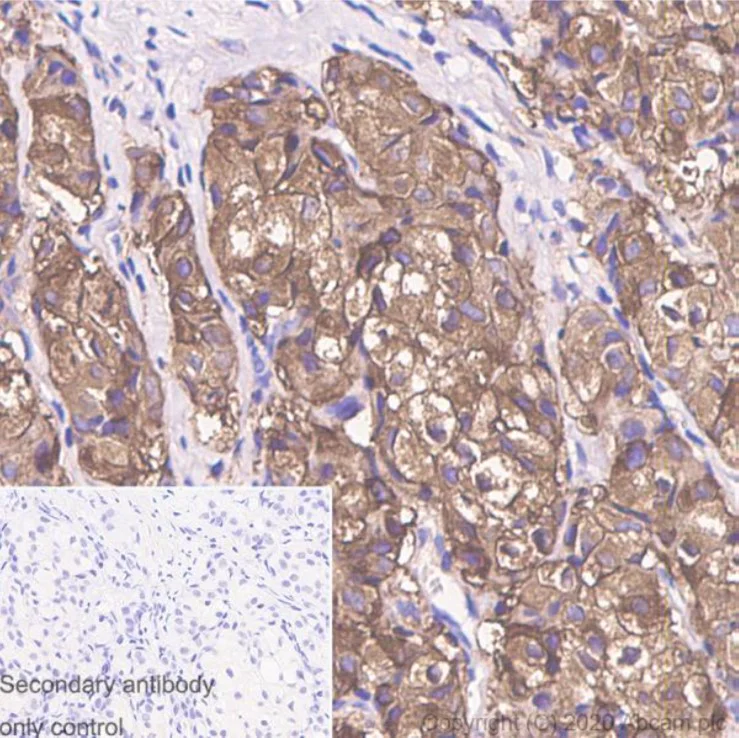

Immunohistochemistry (Formalin/PFA-fixed paraffin-embedded sections) - Goat Anti-Mouse IgG H&L (HRP polymer) (AB214879)

Immunohistochemical analysis of Triple positive breast cancer tissue stained with Ki-67 and detected with ab214879.